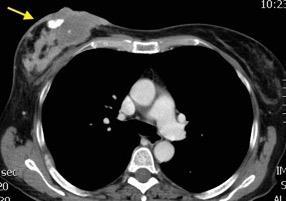

Masa axilar izquierda y derrame pleural derecho. Implantes pleurales, paraespinales . Ganglios en mamaria interna. Linfoma B difuso

Jaffe ES. Diagnosis and Classification of Lymphoma: Impact of Technical Advances.

2005. Masa pulmonar.